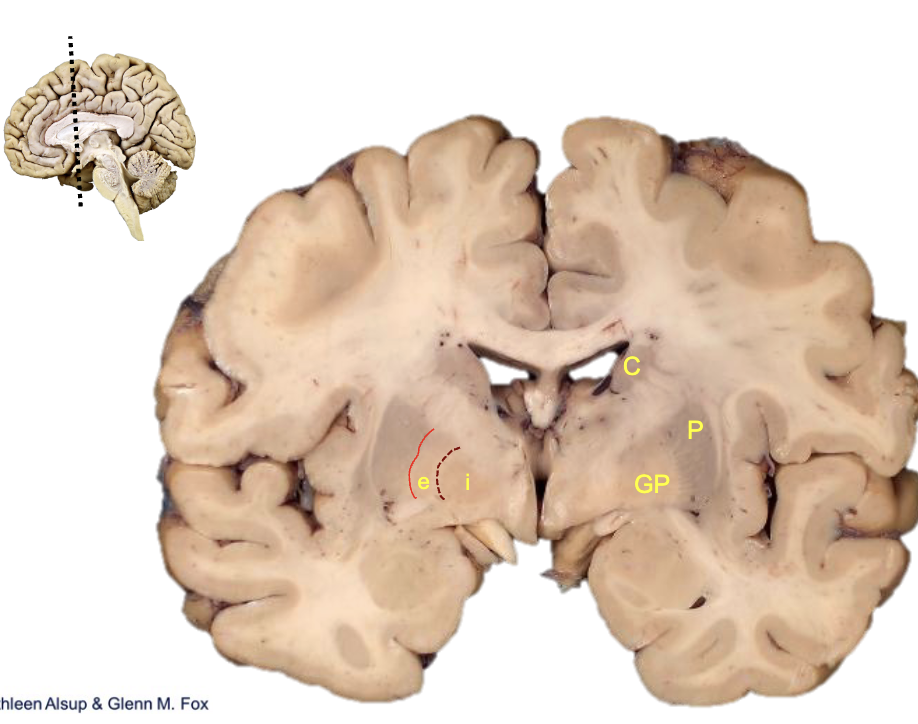

<p><strong>what is c?</strong></p>

what is c?

caudate

<p><strong>what is p?</strong></p>

what is p?

putamen

<p><strong>what is gp?</strong></p>

what is gp?

globus pallidus

<p><strong>what is i?</strong></p>

what is i?

internal segment

<p><strong>what is e?</strong></p>

what is e?

external segment

<p><strong>basal ganglia</strong></p><ul><li><p>______ facilitates appropriate motor programs</p></li><li><p>______ inhibits competing motor programs</p></li></ul><p></p>

basal ganglia

• ______ facilitates appropriate motor programs

• ______ inhibits competing motor programs

direct pathway, indirect pathway